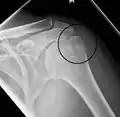

Fracture of the greater tuberosity of the humerus -

Multi-fragmented, or comminuted fracture of the proximal humerus with involvement of the greater tuberosity -

Proximal humerus fracture -